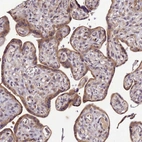

Immunohistochemical staining of human skeletal muscle shows strong cytoplasmic positivity in myocytes.